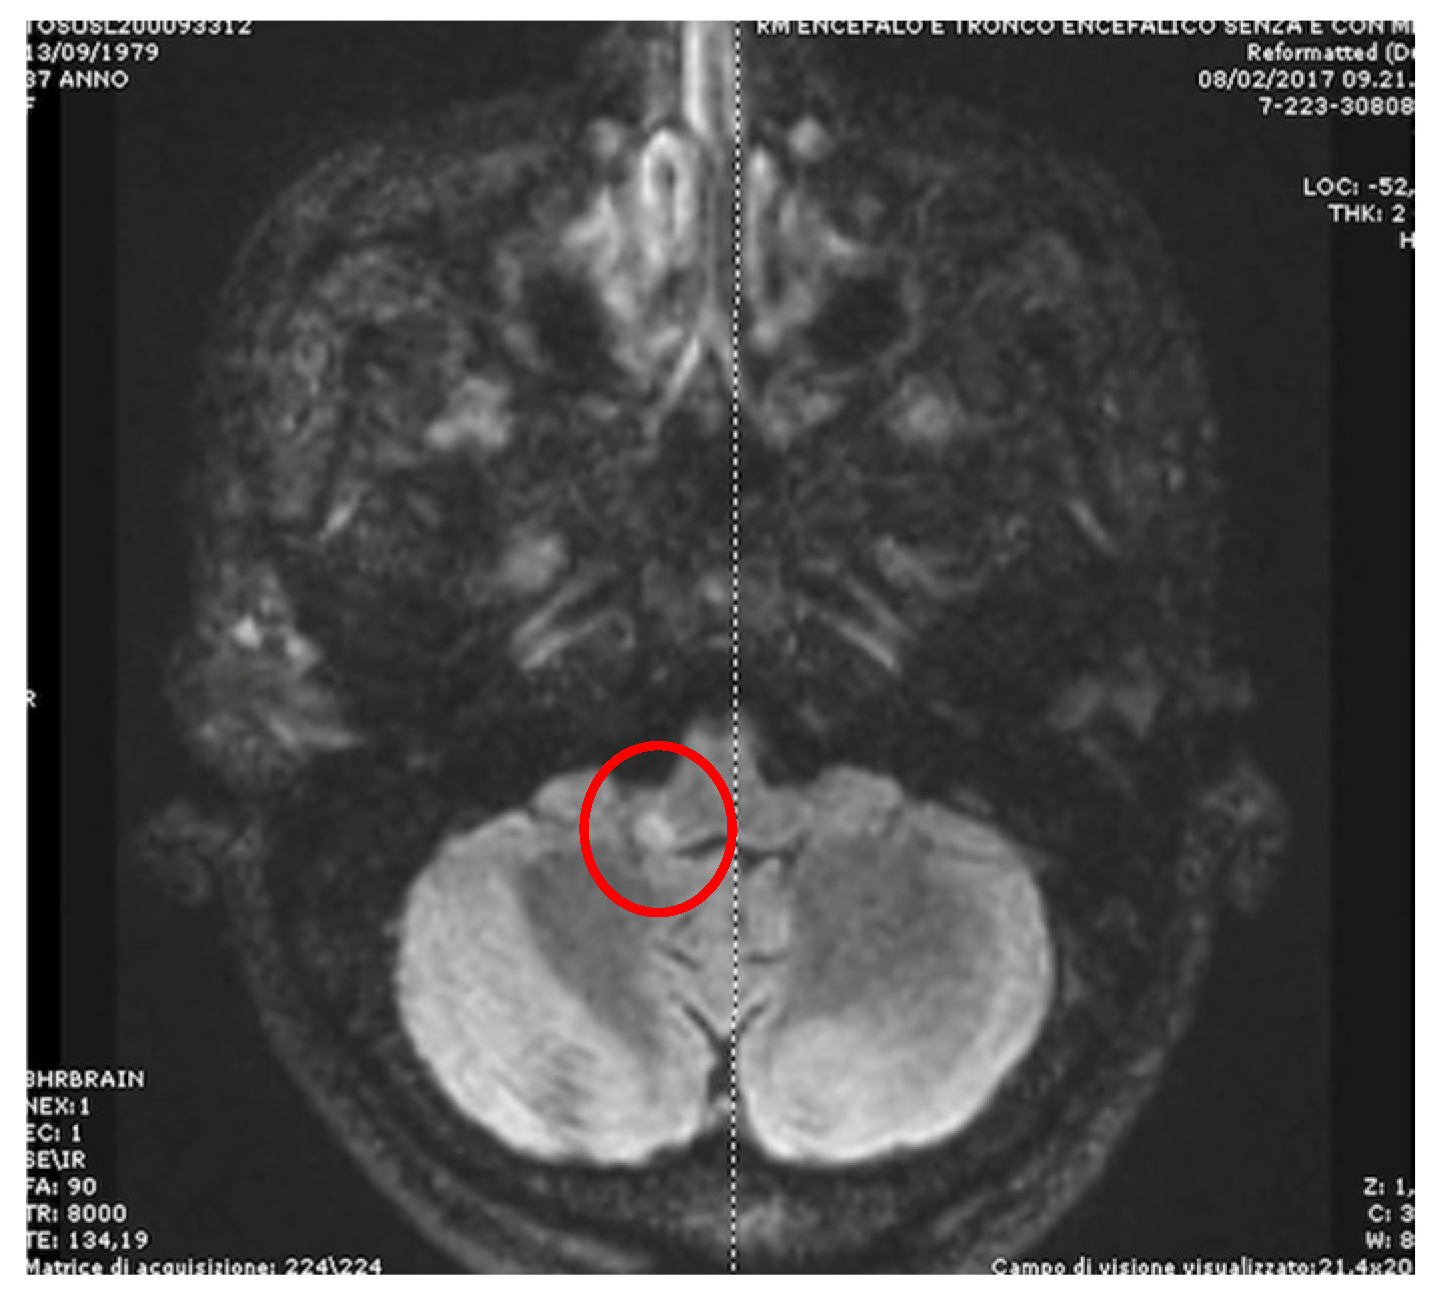

- Apogeotropic bidirectional horizontal nystagmus. More commonly associated with cerebellar disease [56,64], this type of CPN shows no latency and no associated vertigo, lasts as long as the position is maintained, and is reproduced by returning the patient to the same position. A brainstem lesion could induce an apogeotropic CPN because of damage to the connection from the nodulus and uvula (and sometimes tonsil) to the vestibular nuclei [18,58,59,60,61,62,63,64] (Figure 4).